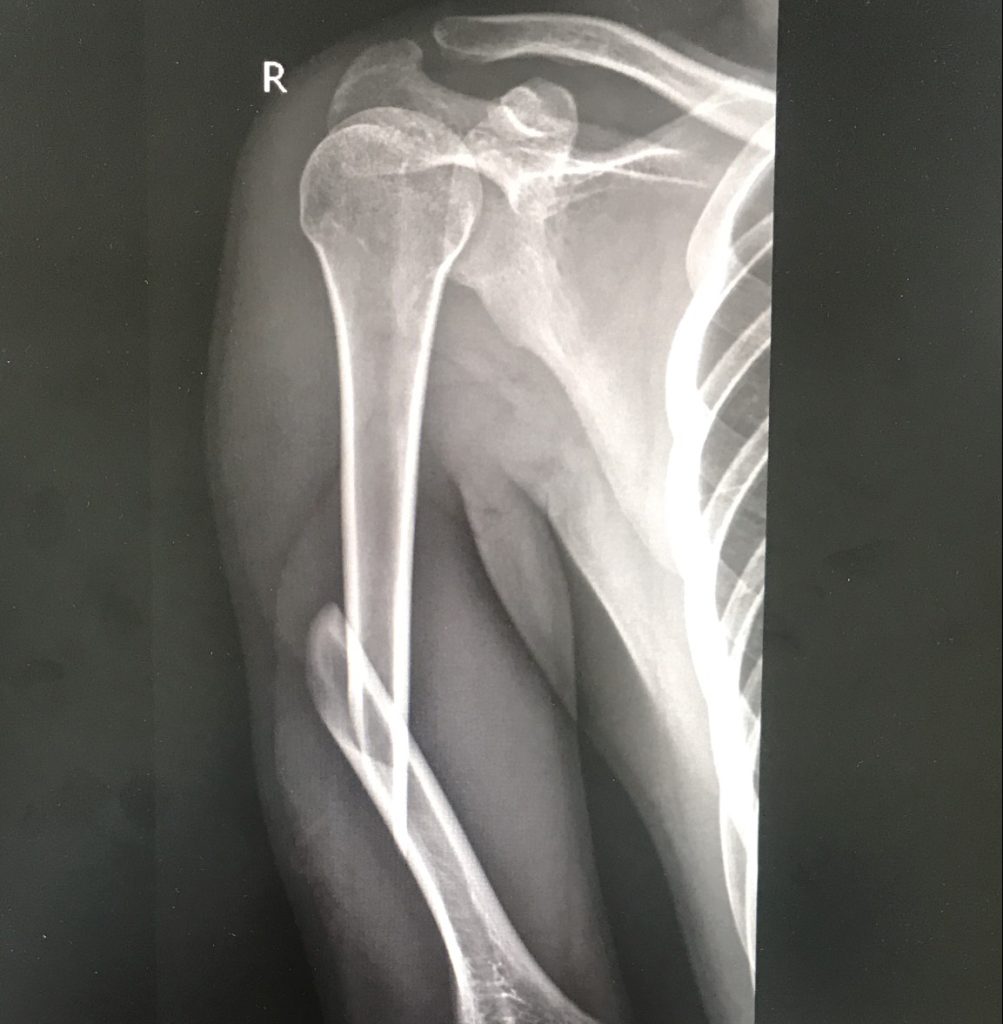

Nhận biết gãy thân xương cánh tay

Gãy thân xương cánh tay

Chụp X-quang: Xác định vị trí, mức độ gãy.

4. Chẩn đoán mức độ gãy xương

Gãy không di lệch: Xương gãy nhưng vẫn ở vị trí ban đầu.

Gãy di lệch: Hai đầu xương tách xa nhau.

Gãy nặng: Gãy nhiều mảnh hoặc có tổn thương phần mềm.